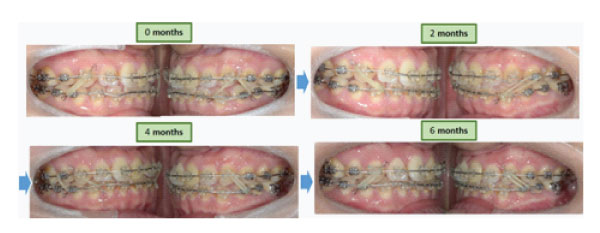

The initial leveling and alignment by 0.016x 0.022 ISW archwire were performed after full mouth direct bracket bonding (0.018inch pre-adjusted bracket). Then, correction of dental crossbite was done by using 0.016x 0.022 ISW archwire. Intermaxillary elastics were used for the establishment of intercuspal interdigitation. Finally, finishing and detailing were done with elastic chains. A stable occlusion and well aligned dentition were achieved.

In this case, dental crossbite was corrected by ISW archwire leveling and expansion

within five months(Figure 8). When the ISW archwire was engaged into the bracket slots, the wire is not a straight line but a curvature, therefore the actual wire length(a+b) is longer than the straight line distance(c)[7-8] (Figure 9). This explains how arch expansion by leveling can be achieved. This is a simple and efficient approach for clinicians.